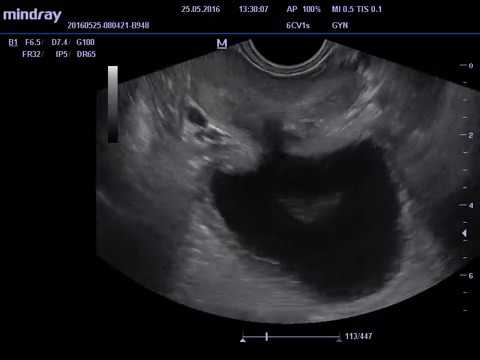

Дивертикул мочеточника: УЗИ-изображения и медицинские примеры